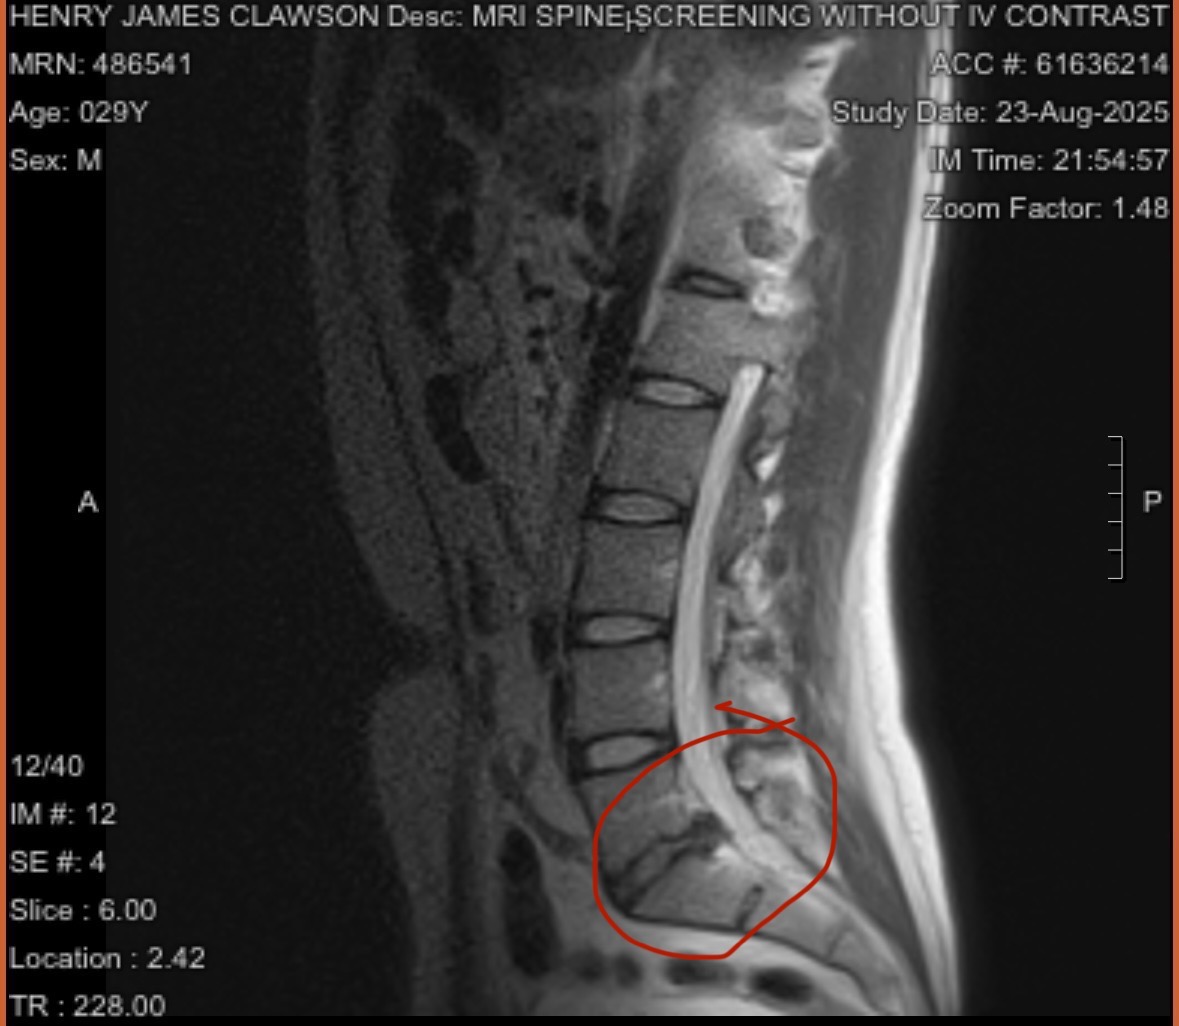

For the past two years, he has lived with a herniated disc that’s been pressing on his spinal nerve, leaving him with constant pain and loss of sensation in his left leg. He’s tried every non-surgical option available—from medications to injections—but nothing is working anymore. The next step is surgery.